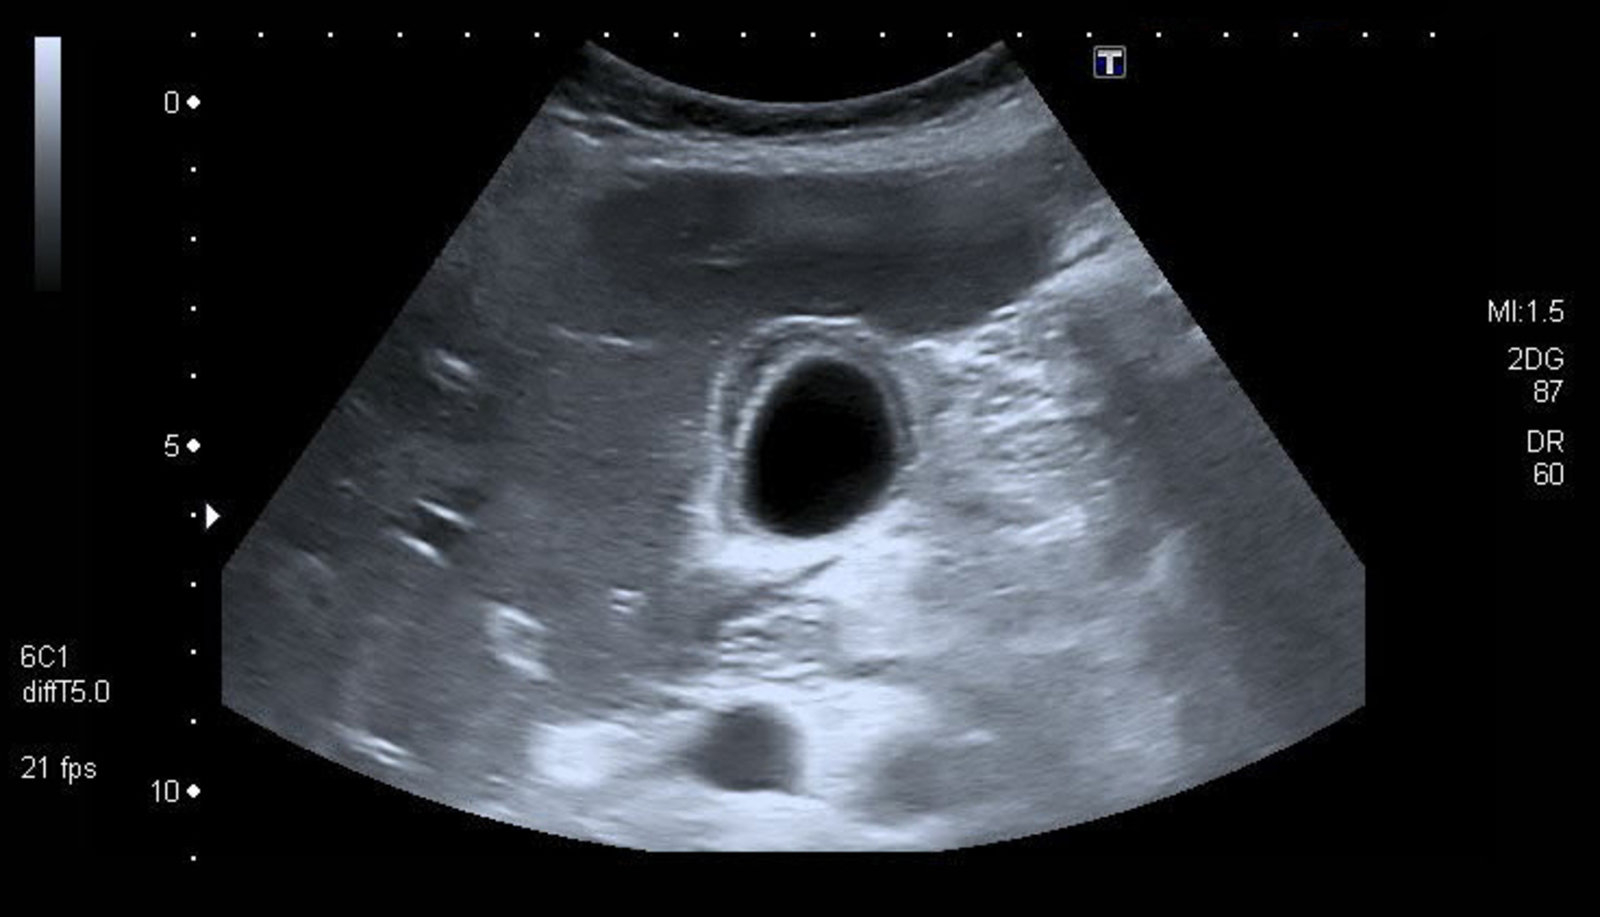

• Ultrasound (first-line):

• Gallbladder wall thickening >4 mm (most specific)

• Pericholecystic fluid

• Gallstones or sludge

• Sonographic Murphy's sign

• Gallbladder distension

• Sensitivity: 81%, Specificity: 83%